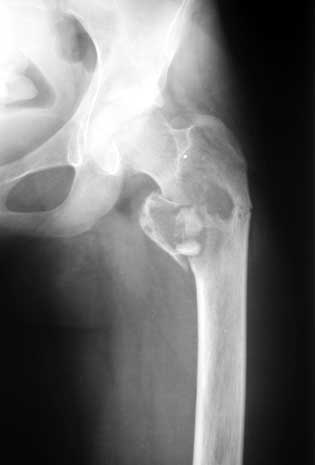

Коллеги,Полтора года назад девочке (сейчас ей 16) была сделана частичная резекция вертельной области с аутопластикой из гребня подвздошной кости.

На днях - патологический перелом (первый снимок). Пока наложена кокситная повязка (второй снимок). Вопрос - как лучше вести больную? Консервативно - оставить в этой же повязке? Остеосинтез? Какой именно? Спасибо. Екатерина А. Озерова, детская ортопедическая клиника УНИИТО